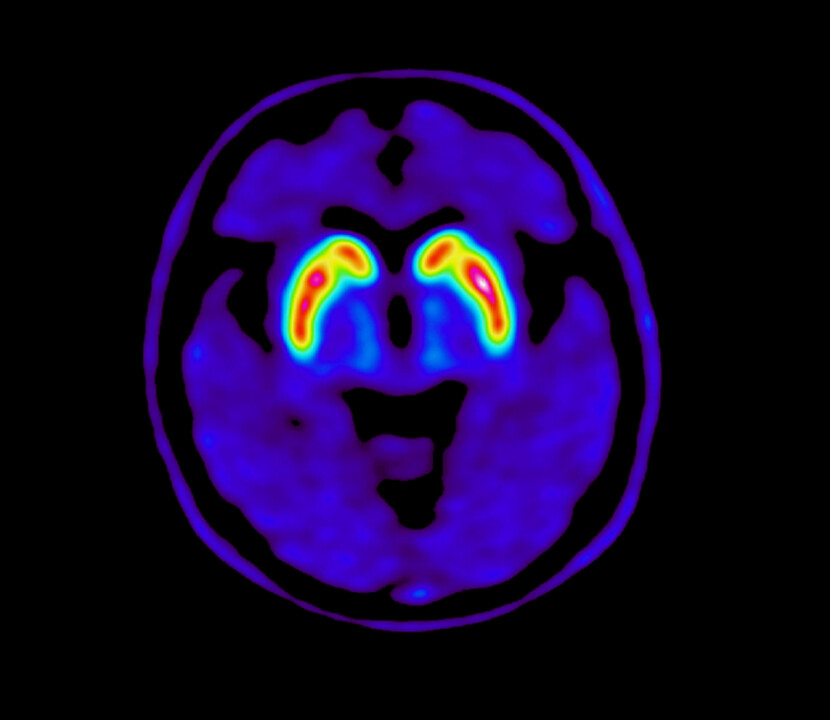

DopaminTransporter-PET in Atypical parkinsonian syndromes and Lewybody Dementia – DaTAtiLDe

Research project Brain imaging of the dopamine function with 18F FE-PE2I PET/CT in Lewy Body Dementa and Atypical Parkinsonian syndromes.

The goal of the research project is to contribute to improved diagnostic accuracy in Lewy body dementia and atypical parkinsonian syndromes through better knowledge about the cerebral dopamine transporter (DAT) availability in patients with neurodegenerative disorders by using detailed PET/CT brain imaging with a highly DAT-selective tracer, 18F FE-PE2I

An isotope-labelled tracer is used for brain imaging of the DAT. Imaging may be done in a gamma-camera with SPECT (e.g. DaTSCAN™). For even more specific and highly detailed DAT-imaging, PET-camera imaging with a very DAT-selective DAT-tracer, 18F FE-PE2I, can be used.

Earlier published data imply that the extent and pattern of dopamine reduction may be different between PS, LBD and APS in early stages. This is, however, not previously studied with 18F FE-PE2I PET.

The superior DAT-selectivity and high resolution in 18F FE-PE2I PET imaging should have all the requirements to detect such differences between these neurodegenerative diseases, which could improve the early differential diagnosis.

In this prospective research study, we will evaluate the distribution of DAT-activity in the basal ganglia in patients with early stage LBD and APS with 18F FE-PE2I PET/CT. We will compare images to previously collected image data from early stage PD-patients and healthy volunteers.  We will also assess the correlation between DAT-activity and glucose metabolism in the striatum.  The study will include 20 patients with clinical criteria for LBD and 20 patients with clinical criteria for APS in 60-80 years of age.